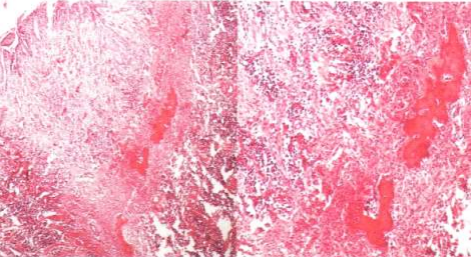

Histopathology

Histopathological examination revealed a delicate connective tissue stroma covered by stratified squamous epithelium which is disrupted at places. The bulk of the lesion is composed of cellular mass of connective tissue comprising of large number of plump proliferating fibroblasts, mixed inflammatory cell infiltrate and mineralized component in the form of interconnecting trabeculae of woven bone. All these features were suggestive of peripheral ossifying fibroma [Figure 6].

Figure 6 : Histopathological Report